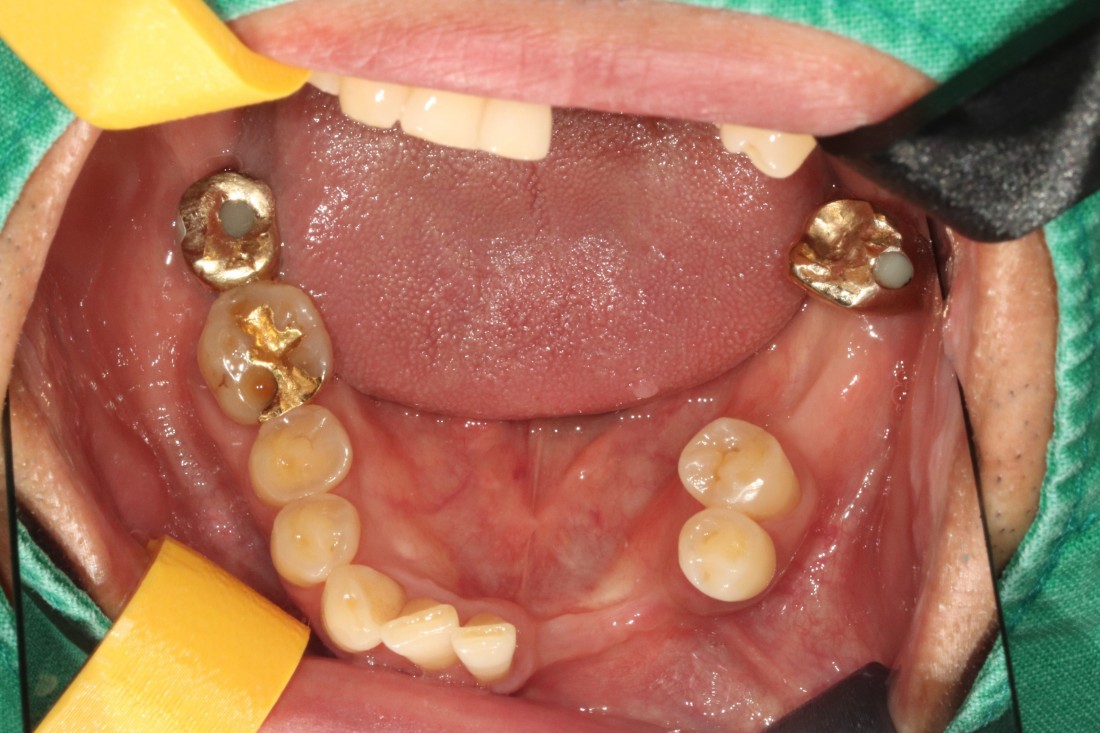

잇몸절개를 최소화 할수록

회복에 걸리는 시간도 매우 적기 때문에

고혈압/ 당뇨 등 기저질환이 있는 분들이나

70대가 넘는 고령의 고객분들도

빠른 회복을 기대할 수 있는

전남광주 임플란트 치과입니다.